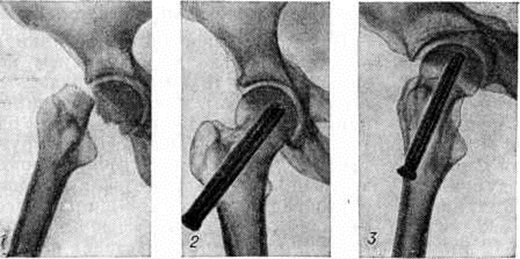

При выборе метода лечения Переломы (особенно оперативного) важно выяснить адаптационно-компенсаторные возможности и резервные силы организма. Пожилым ослабленным больным предпочтительно применять простые, легко переносимые и сравнительно безопасные приёмы лечения. Следует избегать методов лечения, вынуждающих длительно лежать в постели и затрудняющих передвижение. У данного контингента больных значительно возрастает степень операционного риска. Поэтому оперативное вмешательство по поводу Переломы у пожилых людей нужно применять тогда, когда консервативные методы не эффективны, а также в тех случаях, когда оперативный способ может быть легче перенесён больным, чем консервативный. Оперативное лечение наиболее часто применяют при аддукционных (варусных) медиальных Переломы шейки бедренной кости. В этих случаях показан остеосинтез трёхлопастным гвоздём или другим фиксатором, а также эндопротезирование (рисунок 12 и 13). При соответствующих показаниях вертельные и диафизарные Переломы бедра также лечат оперативно.